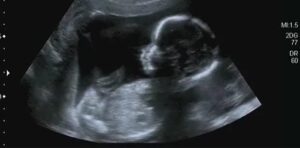

What Does Your Baby’s Ultrasound Image Look Like at 12 Weeks of Pregnancy?

The 12th week of pregnancy is one of the weeks when the baby moves the most. The baby never stops in the womb and moves constantly. This week, your baby is restless and touches almost everywhere. Now, the baby touches places intentionally. There are also movements that the baby performs for the first time this week; for example, in a 12-week pregnancy, your baby opens and closes its jaw as if doing jaw exercises. This movement is innate for the baby, thereby strengthening the jaw muscles. If caught during an ultrasound scan this week, you might even see the baby’s hiccups. Although your baby is opening and closing its jaw, it does not yet know how to swallow.

Your baby moves so much this week that it records every place it touches in its brain. By touching around, the baby must have discovered its lips, as the sucking reflex has developed this week and our baby has started to suck its thumb. If you happen to watch this moment on the ultrasound, it will remain in your mind as a very pleasant image.